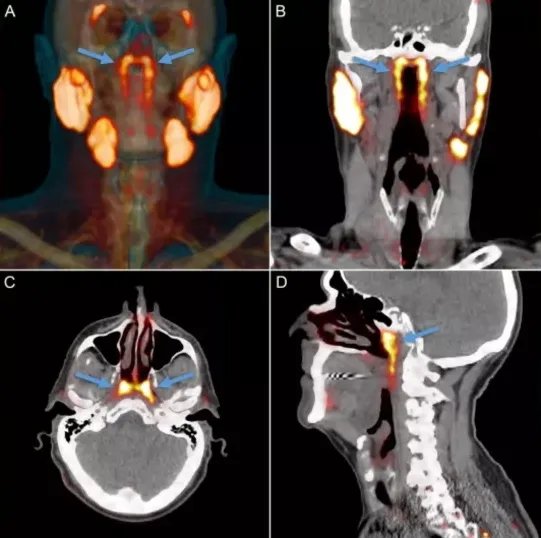

这个器官位于鼻咽区域后面的唾液腺,研究人员用PET-CT扫描前列腺癌细胞时,偶然发现了这一腺体。

在之后针对100名患者的研究中,研究人员证实了这一发现。

他们将这个器官命名为“小管腺”,在给头颈部癌症进行化疗时,需要尽力避开主要的唾液腺,因为这会对患者的吞咽造成影响,但这一新的发现可能可以降低这一副作用的发生。